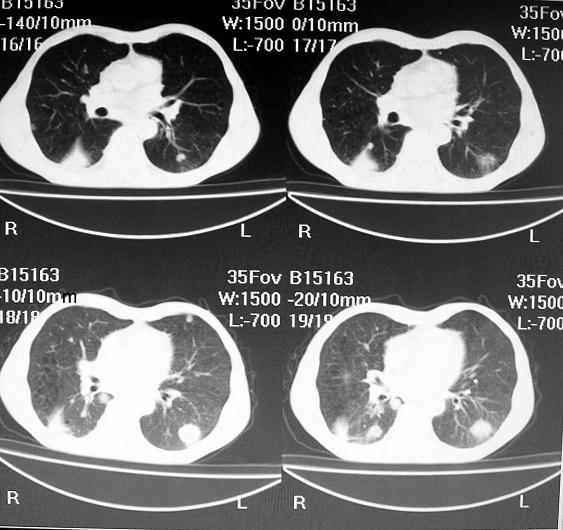

标题: CT10688:男63岁胸痛来诊 [打印本页]

标题: CT10688:男63岁胸痛来诊

男63岁胸痛来诊

右下肺周围性肺ca并双肺及右侧胸膜转移。[emb6]

右肺病灶前缘不平整,略呈分叶状,其后方胸膜下脂线消失且似有向胸壁浸犯,左下肺球形灶内可见不规则空洞影,余双肺内可见多枚结节影,结合病史支持考虑肺癌肺内转移胸膜转移,便双肺后部病灶倒也是结核好发区域,建议穿刺活检